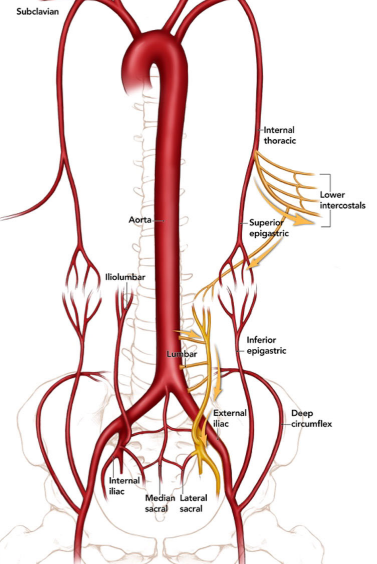

Collatérale de Winslow

- Voie de dérivation lors d’occlusion de l’artère iliaque externe

- Entre l’artère épigastrique supérieure et inférieure

- Subclavière → Mammaire interne → Epg-Sup → Epg-Inf → Iliaque Ext

Collatérale Paralombaires → Artère Circonflexe Iliaque Profonde / Iliaque Interne